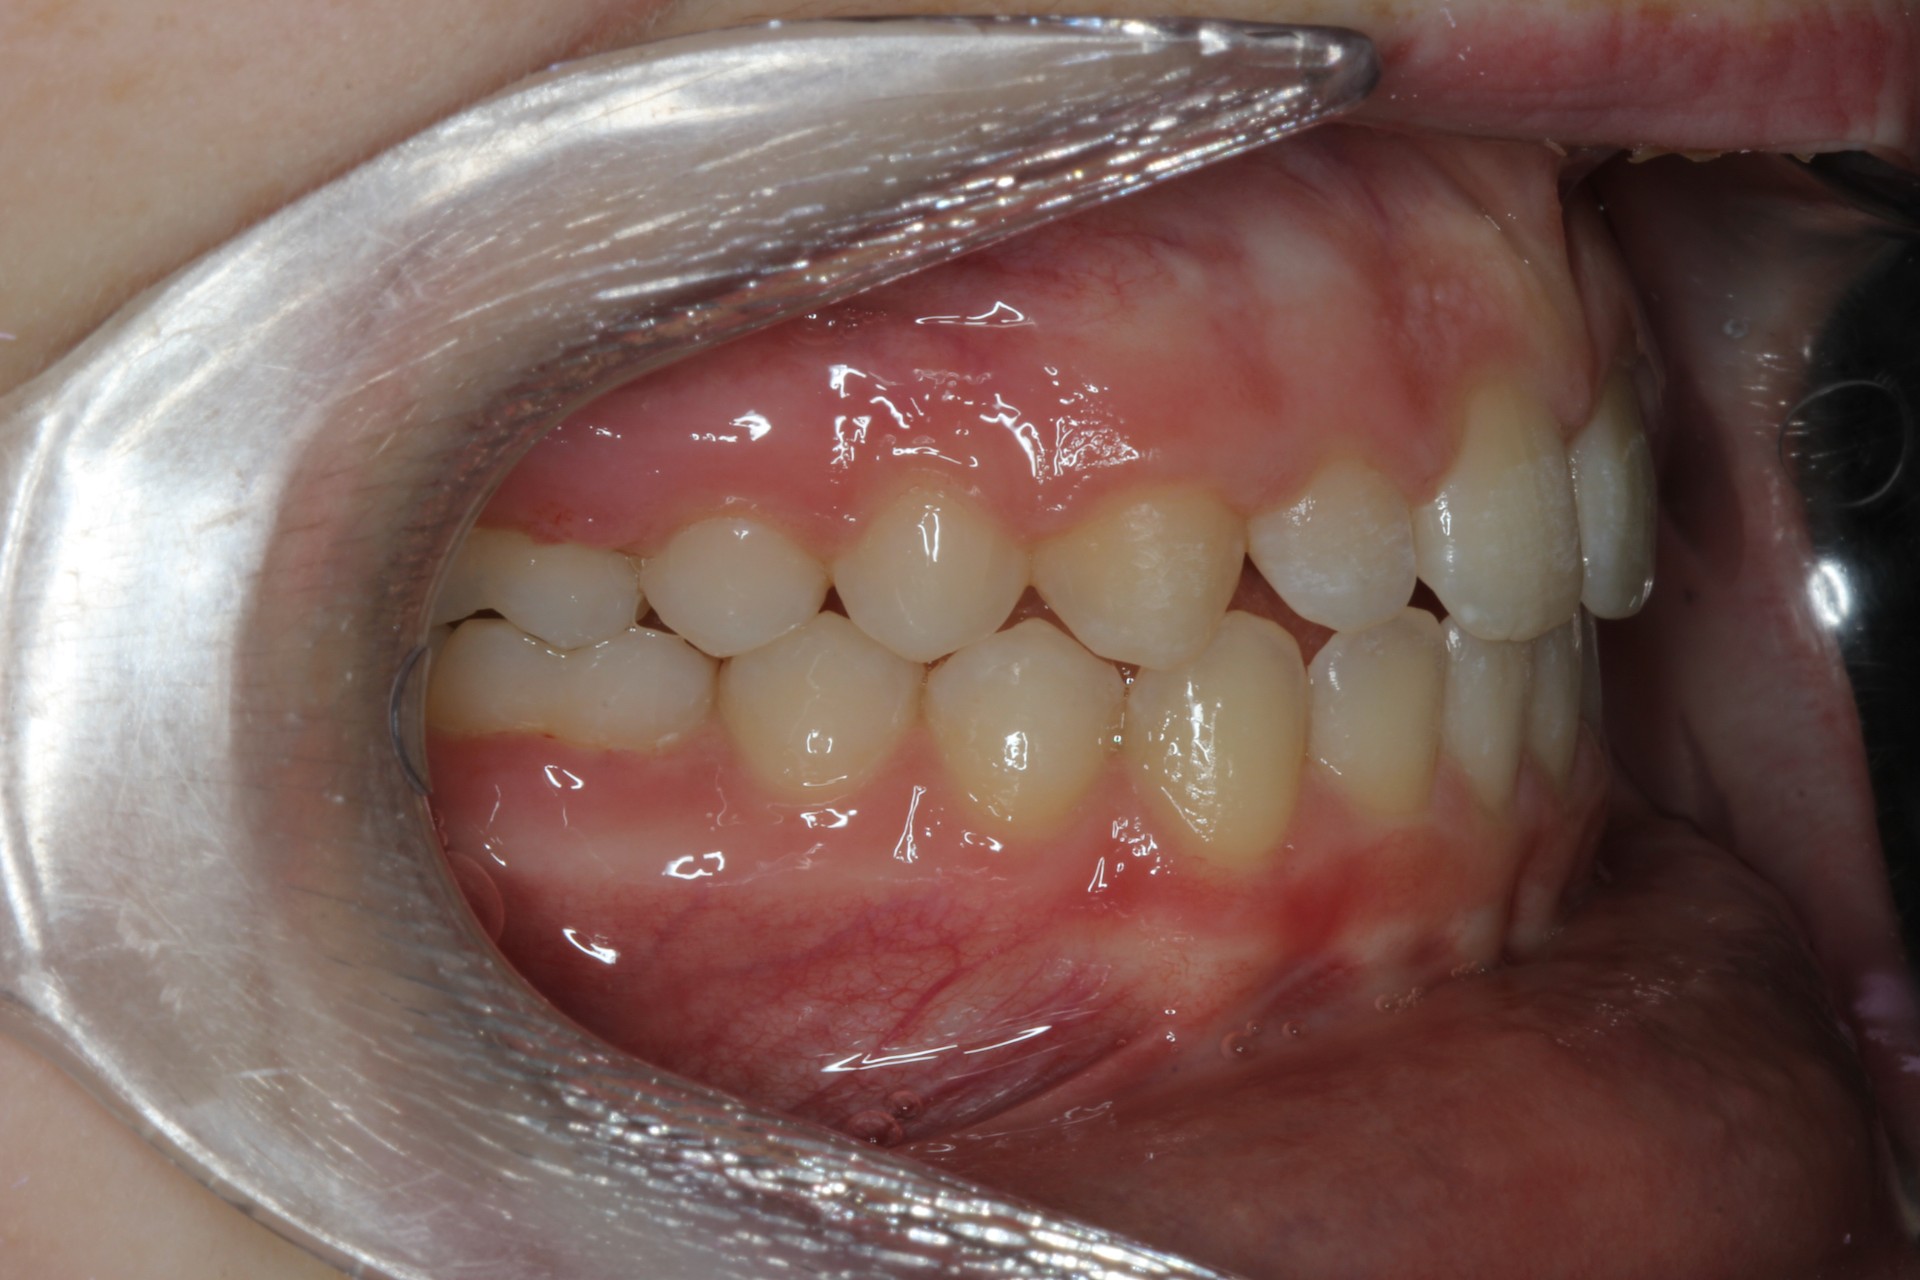

Protruding front teeth – Child case